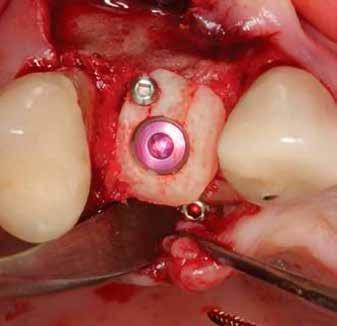

A fogak eltávolítása minimálinvazív módon történt, amelynek során a parodontális rostokat egy periotom segítségével átvágtuk, így lebenyes feltárásra nem volt szükség (3. a–b ábrák) . Az implantátumokat a frissen eltávolított fogak alveolusaiba ültettük be. A foghúzást követően minden alveolust alaposan ellenőriztünk az endodontiai, vagy parodontális eredetű gyulladásos szövetmaradványok eltávolítása érdekében, majd fiziológiás sóoldattal bőségesen átöblítettük. Megfelelő előfúrást követően a kerámiaimplantátumokat 30 fordulat/perc sebességgel és 35 Ncm behajtási nyomatékkal helyeztük be (4. a–b ábrák) . A réseket csontpótlóval töltöttük ki (Maxresorb ® 0,5–1,0 mm szemcseméret, 0,5 cm 3 térfogat, Straumann ®; 6. ábra ).

Azonnali ideiglenes fogpótlás

A műtétet követően önkötő akrilátból ideiglenes koronákat készítettünk, amelyeket cementtel rögzítettünk a cirkónium-dioxid ideiglenes fejeken (CR Zi Pillar®, 7. a–c ábrák ).

Javasolt, hogy a lehető legpontosabban ragaszkodjunk a hangár technika műtéti protokolljához. Miután a csontlemezeket oszteoszintézis csavarokkal rögzítettük, az okkluzális csontlemezt egy trepán fúróval átfúrjuk (lehetőleg az implantátum átmérőjével megegyező méretben), majd az imp-

lantátumot ezen a nyíláson keresztül helyezzük be a korábban előfúrt helyre, amelyet előtte autológ csontrészecskékkel töltünk fel.

13. ábra: Az eltávolítást követően a lemezeket a Safescraper segítségével tovább vékonyíthatjuk. – 14. ábra: A csontlemezt (domború oldalával felfelé) oszteoszintézis csavarral rögzítjük, majd a behelyezendő implantátumnak megfelelő átmérőjű trepánfúróval perforáljuk. – 15. ábra: A hézagokat autológ csontszemcsékkel töltjük ki. – 16. ábra: A csontszemcséket a defektus kontúrján belül helyezzük el. – 17. ábra: Visszahelyezzük az okkluzális csontlemezt. – 18. ábra: Gondoskodni kell az okkluzális csontlemez stabil rögzítéséről. – 19. ábra: Az implantátumot subcrestalisan helyezzük be, majd behelyezzük a zárócsavart.